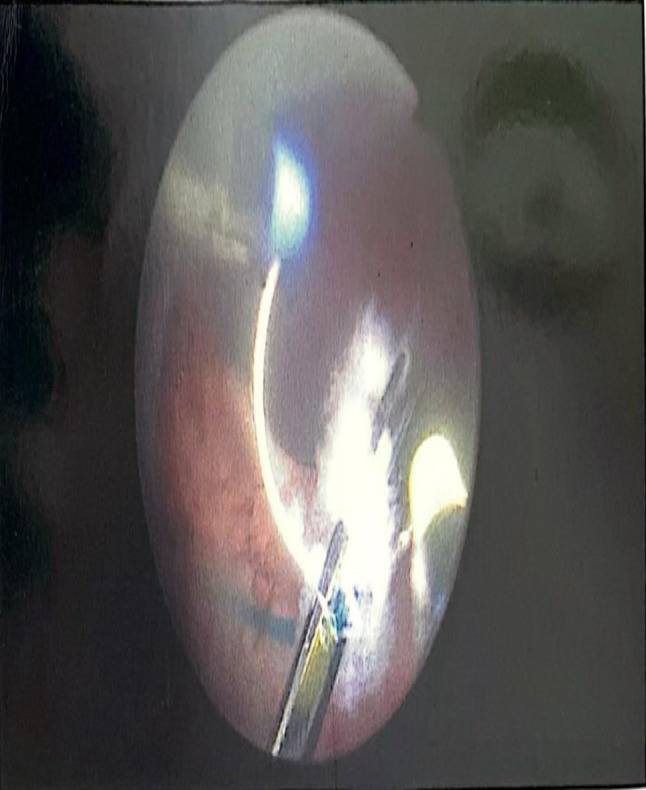

Results: The study included 40 patients with a mean age of 68 (SD ± 8.91) years with moderately enlarged prostates (mean volume 81.56 mL, (SD ± 25.32), and median PSA 3.2 ng/dL). Five patients were presented initially with an indwelling Foley catheter, so their data were not included in the statistical analysis. After Aquablation, the mean IPSS improved from 24.7 (SD ± 7.63) at baseline to 9.8 (SD ± 2.55) (p < 0.0001), the mean Qmax increased from 9.6mL/sec (SD ± 5.76) at baseline to 20.8mL/sec (SD ± 6.28) (p < 0.0001), and the mean PVR decreased from 143mL (SD ± 104.89) at baseline to 36mL (SD ± 30.63 ) (p < 0.0001). The hospital stay for patients admitted ranged from 1 to 2 days. Moreover, there were no major intraoperative difficulties removing dislodged Urolift clips with a loop resectoscope at the end of the procedure, while non-dislodged clips were left in situ. None of the patients had postoperative bleeding that required hospital admission or blood transfusion following discharge.

Abstract Image